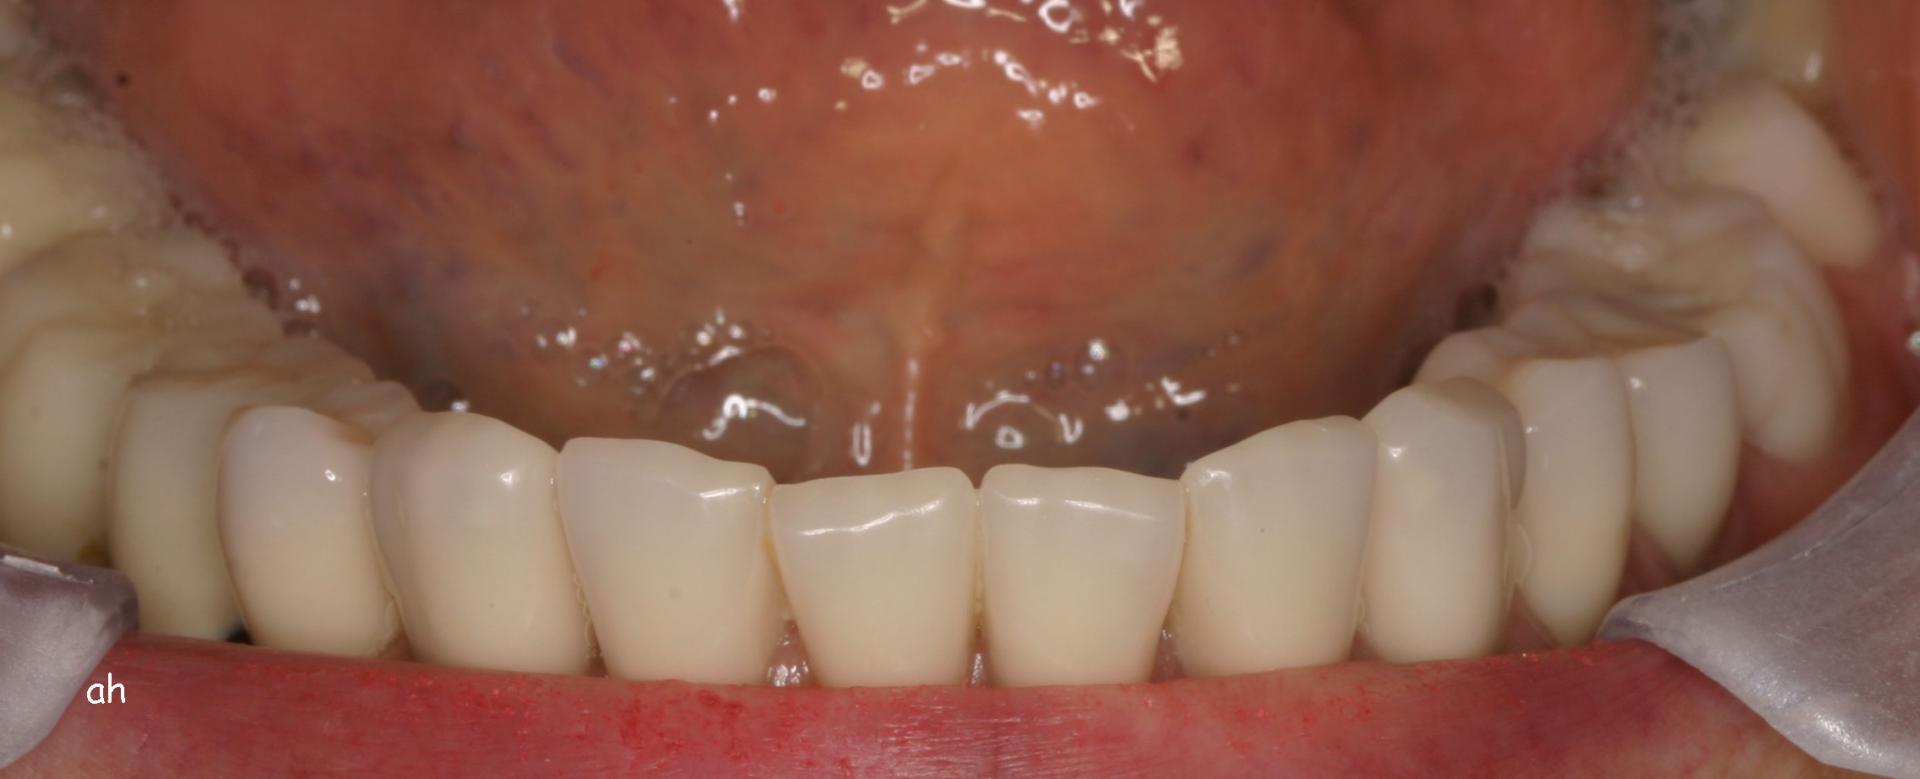

Exemple 1: Ce patient a perdu son incisive centrale gauche lors d'un accident. Un implant a été posé

Exemple 1: L'implant remplace la racine de la dent manquante

Exemple 1: L'implant s'est intégré dans l'os, une empreinte est effectuée. Le laboratoire peut réaliser la couronne en céramique.

Exemple 1: résultat final.